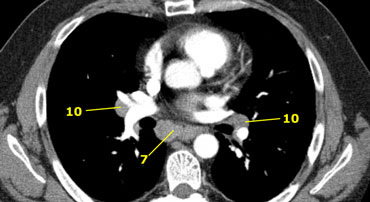

Axial CT anatomy

Images by Dr. Aurelia Fairise of the Institut de Cancérologie de Lorraine in Nancy.

7. Dưới carina

10. Rốn phổi

7. Hạch dưới carina

Nằm ở phía dưới góc carina của khí quản, nhưng không liên quan với thùy dưới hoặc thùy trên của phổi.

Ở bên phải chúng kéo dài đến bờ dưới của phế quản trung gian.

Ở bên trái chúng kéo dài đến bờ trên của phế quản thùy dưới.

10. Hạch rốn phổi

Hạch gần thùy phổi, xa màng phổi trung thất và nằm gần phế quản trung gian bên phải.

Hạch 10-14 thuộc nhóm N1 vì không nằm trong trung thất.